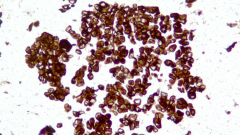

| Description | CLDN18.2是Claudin蛋白質(zhì)家族的一員,位于細胞膜表面,Claudin18.2(CLDN18.2)表達具有特異性。其作為Claudins蛋白的一個亞型,在正常組織中僅表達于分化的胃黏膜上皮細胞。在胃癌、食管癌和胰腺癌等多種腫瘤中表達,并且不僅限于原發(fā)病灶,在轉(zhuǎn)移灶中也有表達。目前臨床研究中使用的檢測方法均為免疫組化。 |

| 示例 | ![]() |

| IHC染色結(jié)果 | |